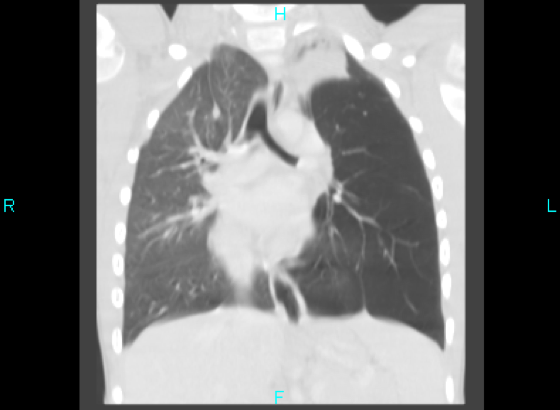

A computed tomography (CT) scan with contrast showed a nodular endobronchial lesion in the left mainstem bronchus with left upper lobe and lingular atelectasis and a hyperinflated left lower lobe. An azygos fissure was noted in the right lung (Figure 2).

Figure 2. Coronal contrast CT image showing a nodular endobronchial lesion in the left mainstem bronchus with left upper lobe and lingular atelectasis and a hyperinflated left lower lobe. An azygos fissure was noted in the right lung.